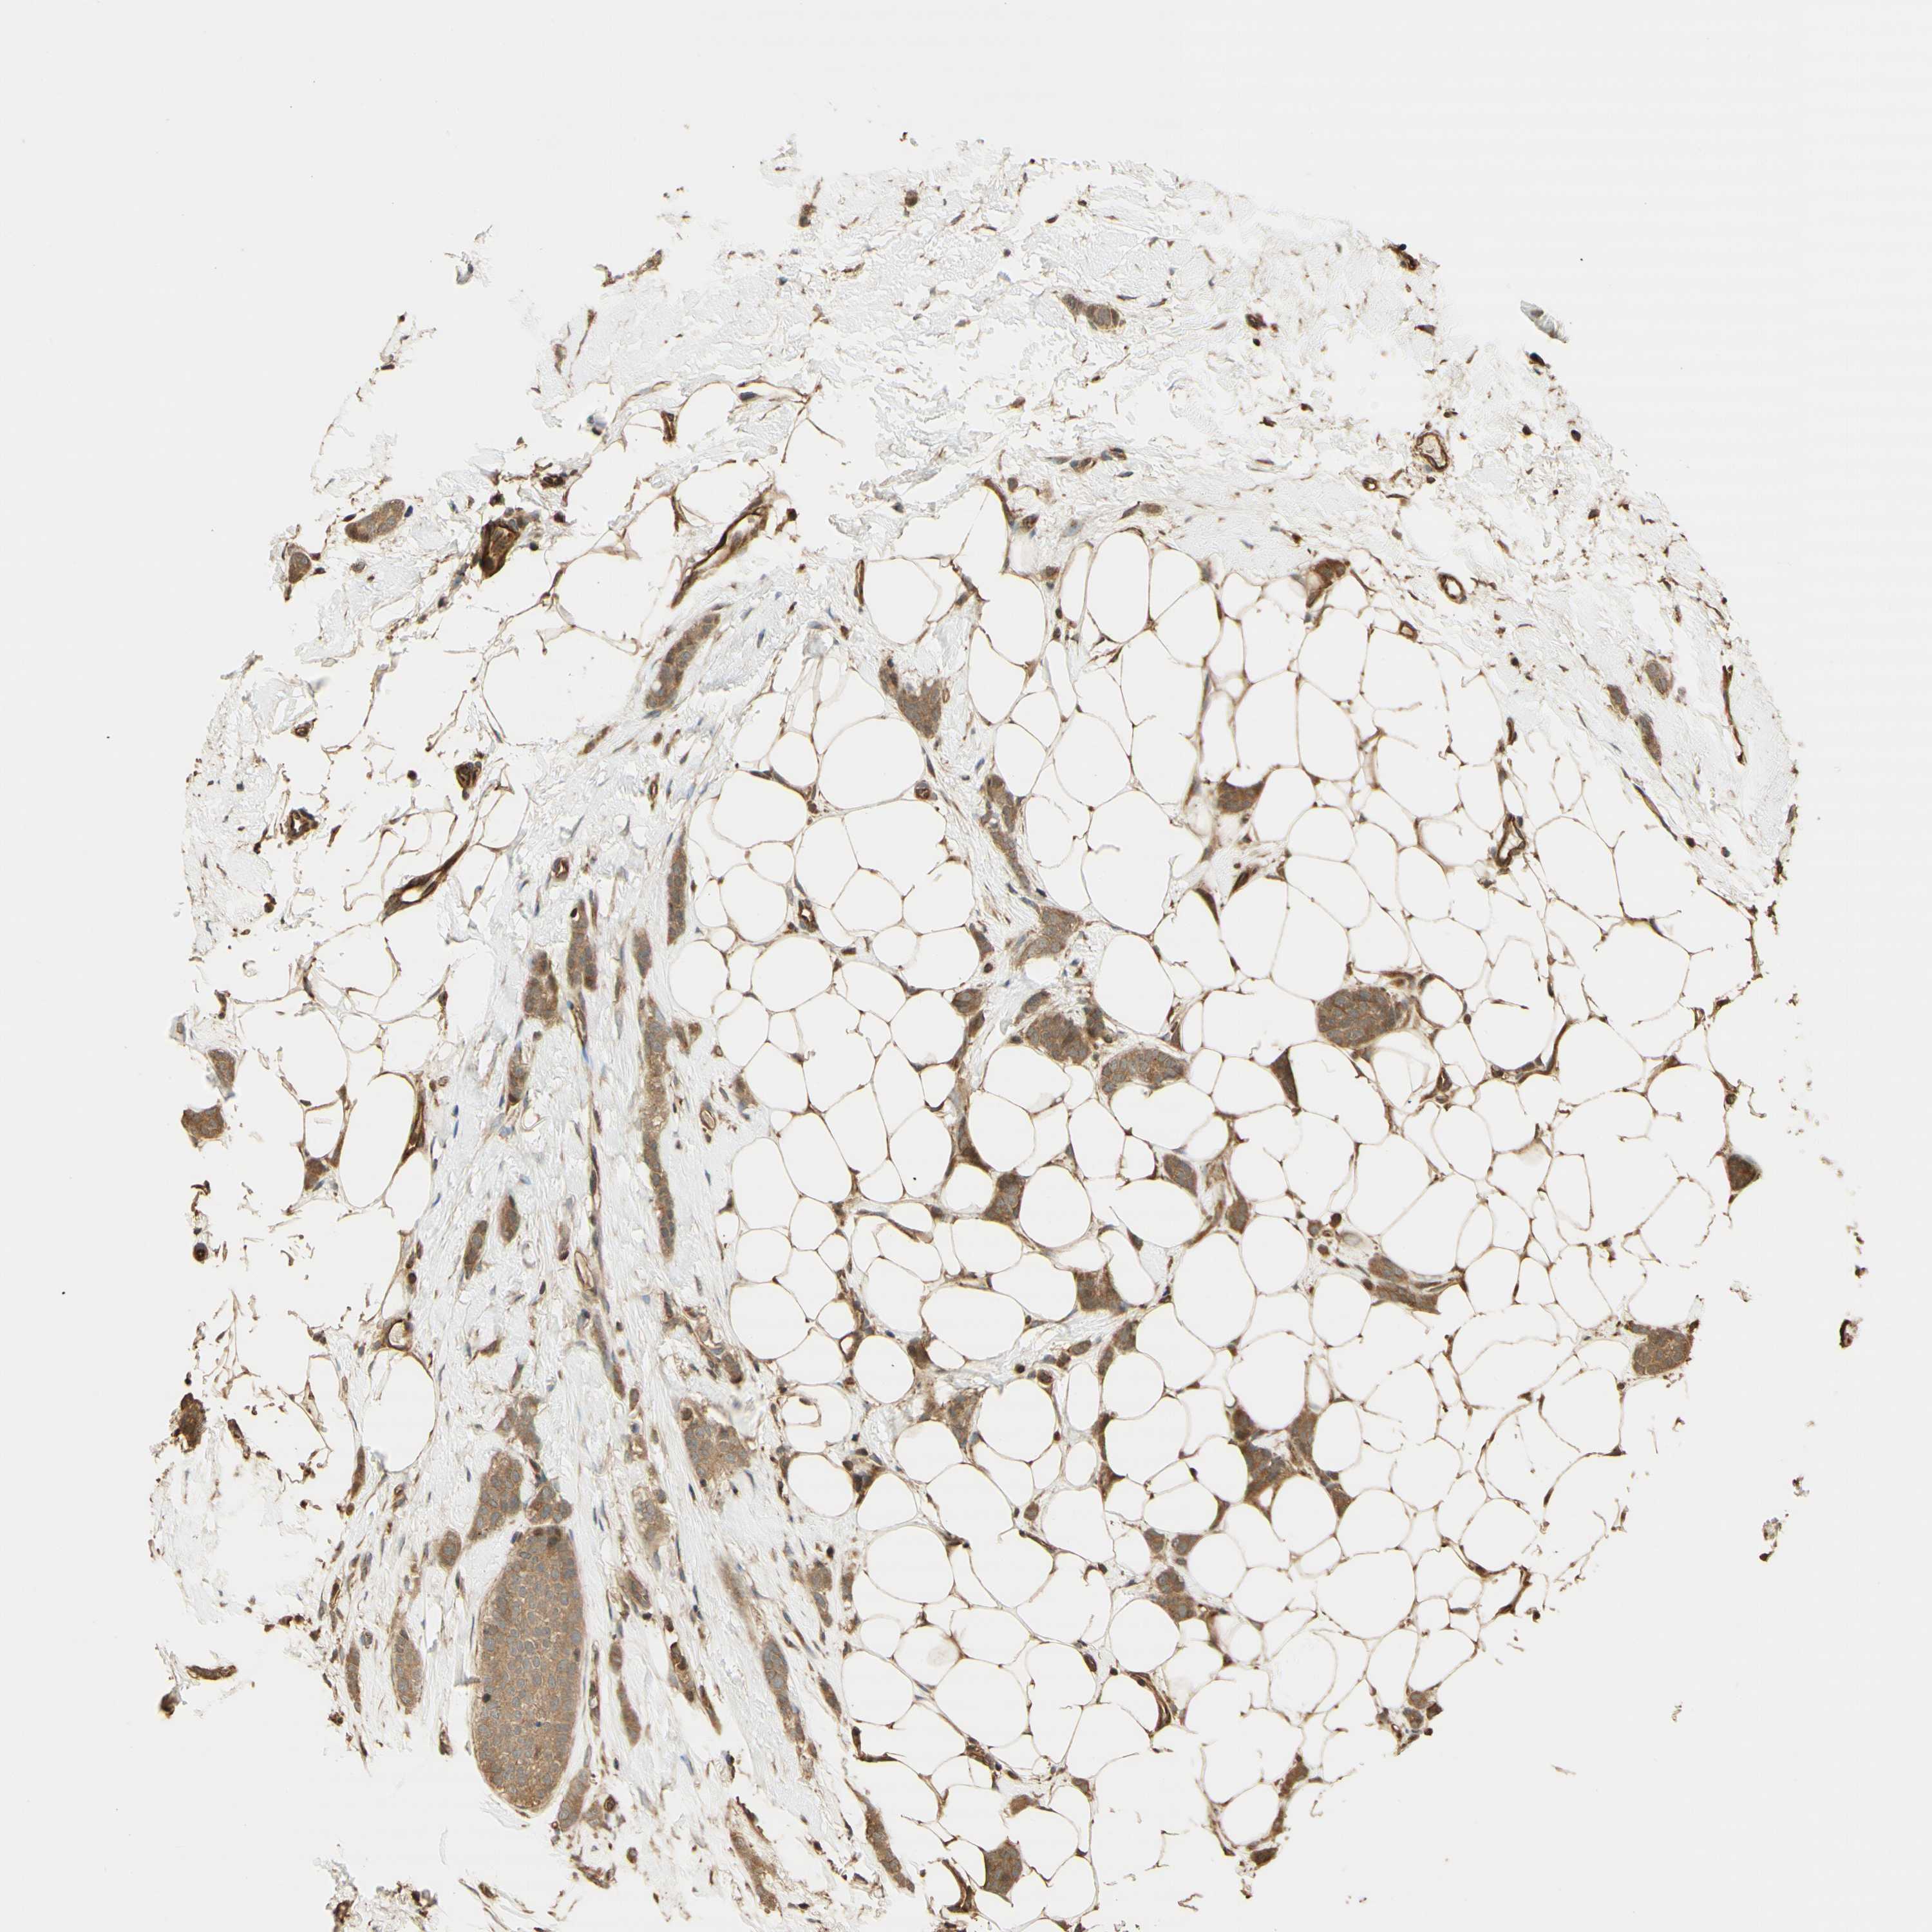

CANCER BREAST CANCER Show tissue menu

BRCA TCGA BRCA VALIDATION PROTEIN EXPRESSION

ANTIBODIES

AND

VALIDATION